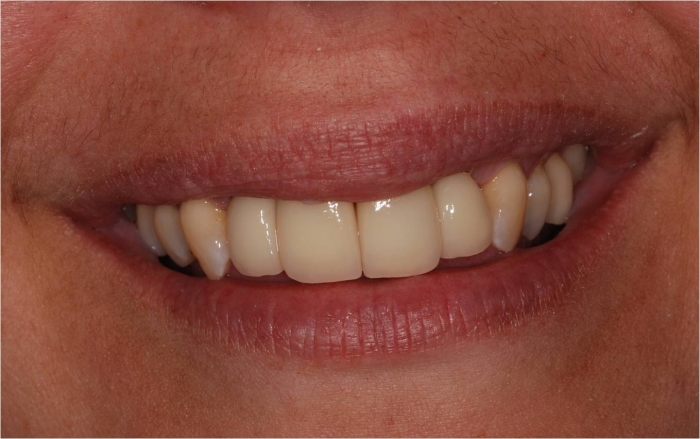

Sorriso final, do caso terminado em abril de 2013